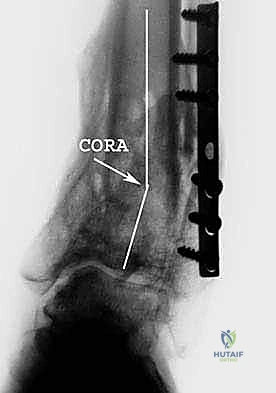

- الأشعة السينية الحاملة للوزن (Weight-bearing X-rays): وهي خطوة حاسمة. يجب أخذ صور الأشعة والمريض واقف، ليتمكن الدكتور هطيف من رسم المحاور الميكانيكية بدقة وحساب زاوية التشوه بالدرجات.

- التخطيط الرقمي: باستخدام برامج حاسوبية متقدمة، يقوم الدكتور هطيف بمحاكاة العملية الجراحية على الكمبيوتر قبل دخول غرفة العمليات، لتحديد حجم الإسفين المطلوب ومكان القطع بدقة مليمترية.

باستخدام أدوات قطع عظمية دقيقة جداً (مناشير جراحية متأرجحة)، وتحت توجيه جهاز الأشعة السينية المباشر في غرفة العمليات (C-arm)، يتم إحداث القطع في عظم الظنبوب في المكان المخطط له مسبقاً، مع الحفاظ على جزء بسيط من القشرة العظمية في الجهة المقابلة لتعمل كمفصلة (Hinge).

يتم فتح القطع العظمي بلطف وتدريجياً للوصول إلى الزاوية المصححة التي تم حسابها. هذه الخطوة هي جوهر العملية، حيث يتم استعادة المحور الميكانيكي السليم للساق.